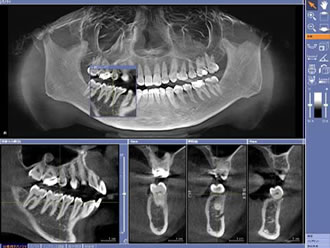

従来のレントゲンでは平面的な撮影しか行うことができず、骨の様子などが詳しく分かりませんでした。しかし、CTスキャンでは3D撮影が可能ですので、インプラントを埋め込む際に必要な、正確な骨の形状・神経や血管の位置などが詳細に分かることで、安全なインプラント治療が可能になります。

CT撮影

立体的に様々な角度から詳しく見ることができます。

CT撮影 横断面

神経や骨の様子が詳しく分かります。

CT撮影 上断面

歯の間隔を詳しく見ることができます。

CT撮影したデータと口腔内を象りして作られた模型を合成することで、詳細な分析が可能となり顎骨や骨の密度の把握、治療前に担当医が3D上でインプラントの仮置きシミュレーションができるため安全性だけではなく完成度の高い治療が可能になります。

iCAT分析ソフト

多角的な分析が可能です。